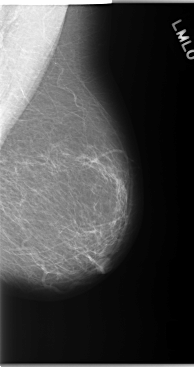

C_0143_1.LEFT_CC

LEFT_CC LINES 5944 PIXELS_PER_LINE 2960 BITS_PER_PIXEL 12 RESOLUTION 50 NON_OVERLAY